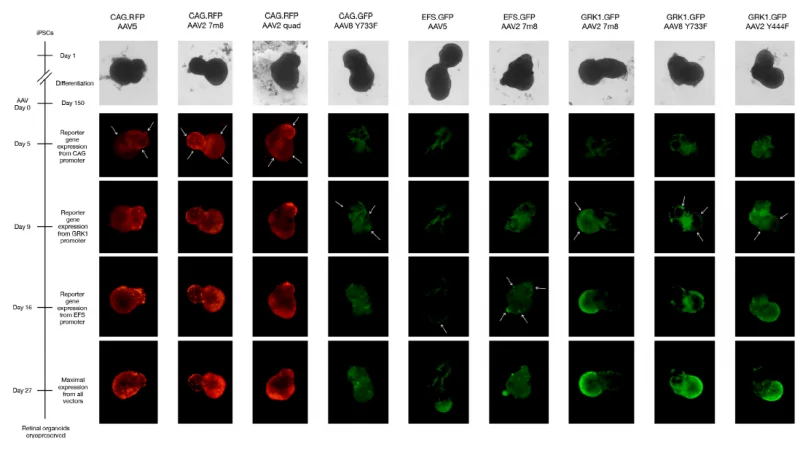

Organoids have been utilized to screen AAV gene therapy vectors in cooperation with a group at the University of Oxford. This study demonstrated the enhanced transduction capability of AAV2 7m8 in retinal organoids when employing the ubiquitous CAG promoter, confirming robust and efficient transduction of human photoreceptor-like cells by AAV vectors.

The experiments demonstrated that a CAG-driven transgene transduced various cell types, whereas GRK1-driven transgenes exhibit a more limited photoreceptor-specific expression (A). This was because the organoids contained multiple cell types, which allowed the experiments to display the targeted cell types specifically. The study also showed that AAV transduction did not affect the retinal organoids’ viability (B).

(A) Live cell imaging of reporter gene expression up to 27 days post-transduction. Arrows indicate the areas where the onset of reporter gene expression first appeared, allowing evaluation of which cell types each AAV vector transduced preferentially. Image Credit: Newcells Biotech